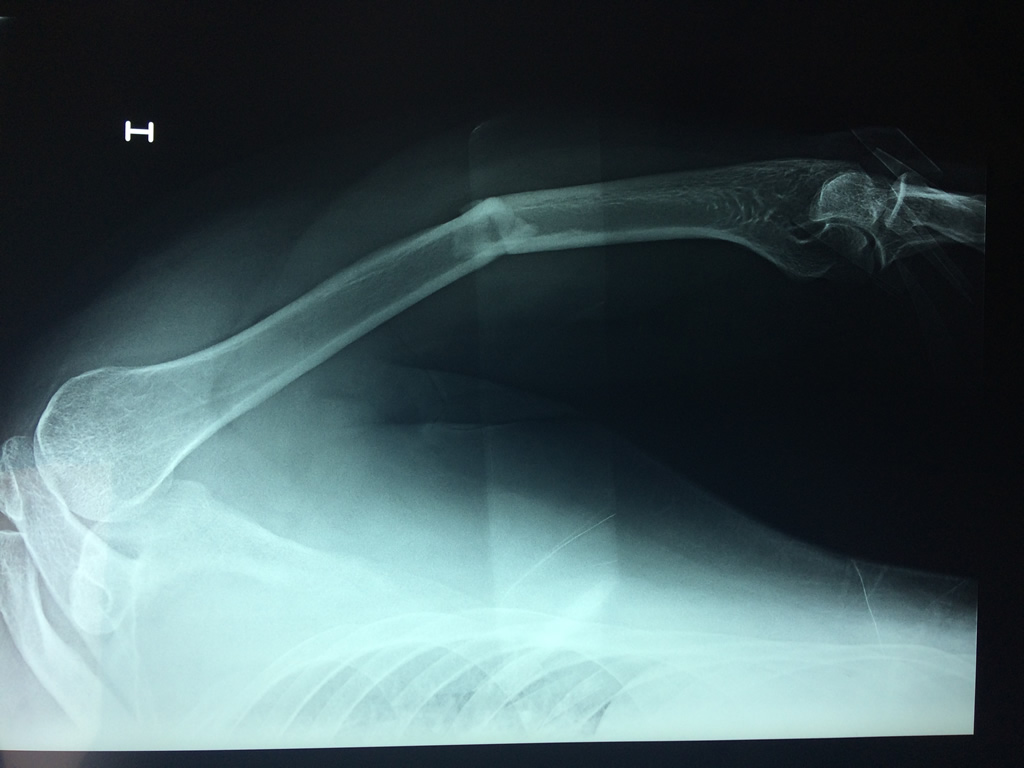

Fémur - Húmero

El Húmero (en latín, humerus) es el hueso más largo de las extremidades superiores en el ser humano. Forma parte del esqueleto apendicular superior y está ubicado en la región del brazo. ... El extremo proximal del húmero tiene la cabeza, cuellos quirúrgico y anatómico y tubérculos mayor y menor.